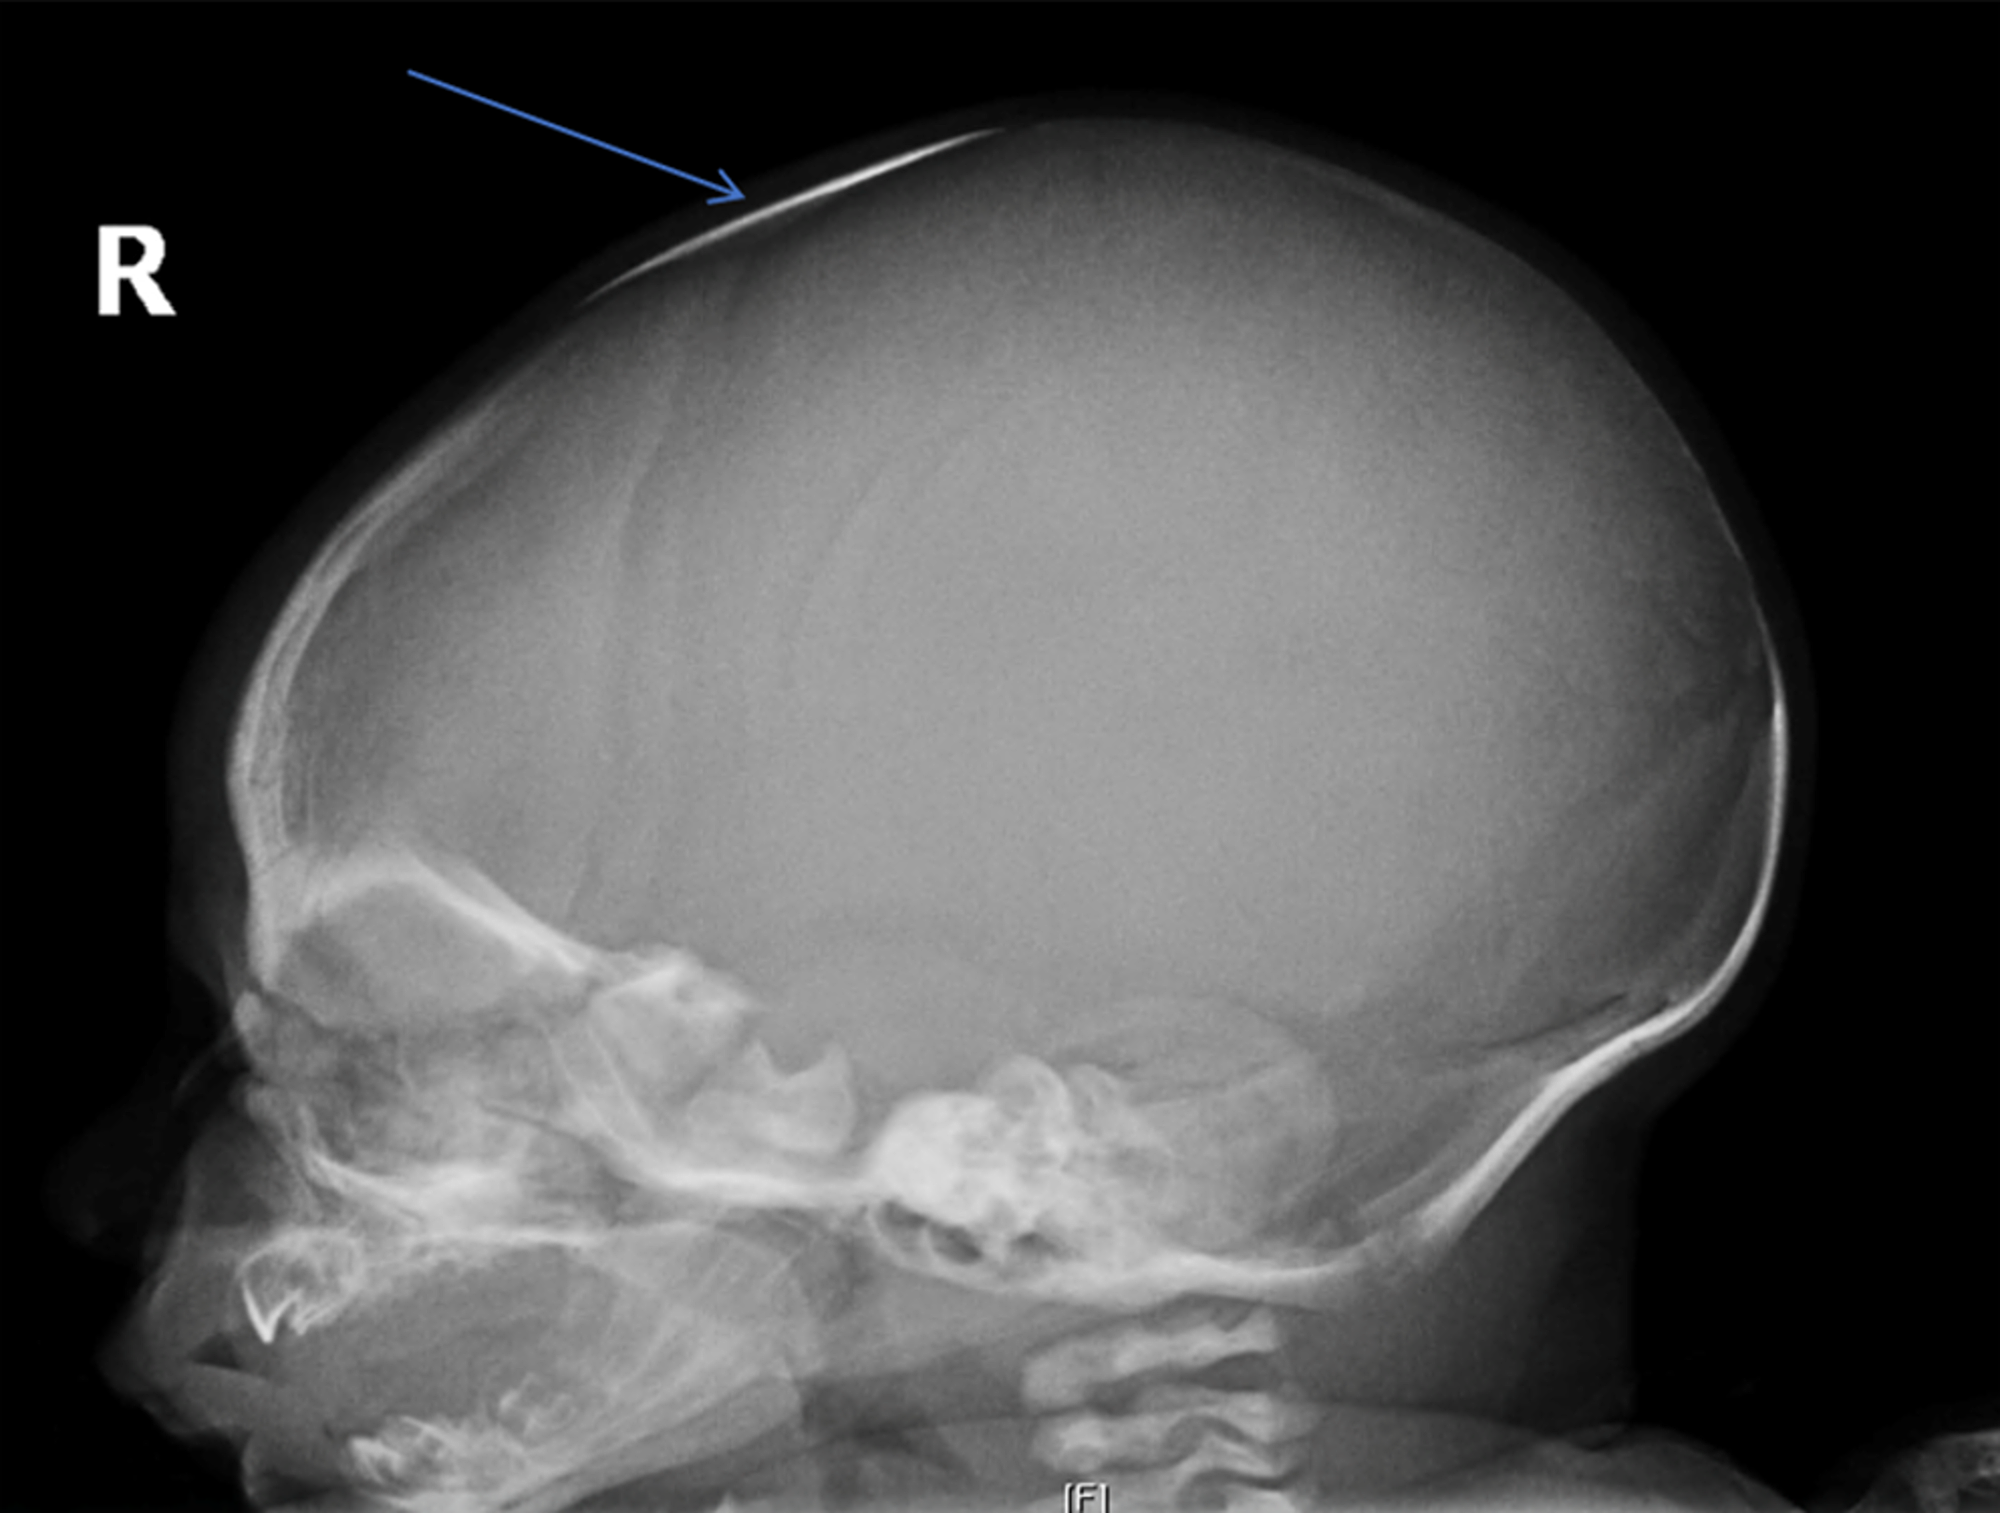

Open anterior fontanelle (pink triangle); nonpneumatized frontal and How Long Is The Anterior Fontanelle Open while the anterior fontanelle typically closes around 18 to 24 months, the posterior fontanelle closes relatively earlier within. Increased intracranial pressure, hypothyroidism, and. The most common causes of a large anterior. range of normal closure of the anterior fontanelle is 4 to 26 months. the average size of the anterior fontanel is 2.1 cm, and the median. How Long Is The Anterior Fontanelle Open.